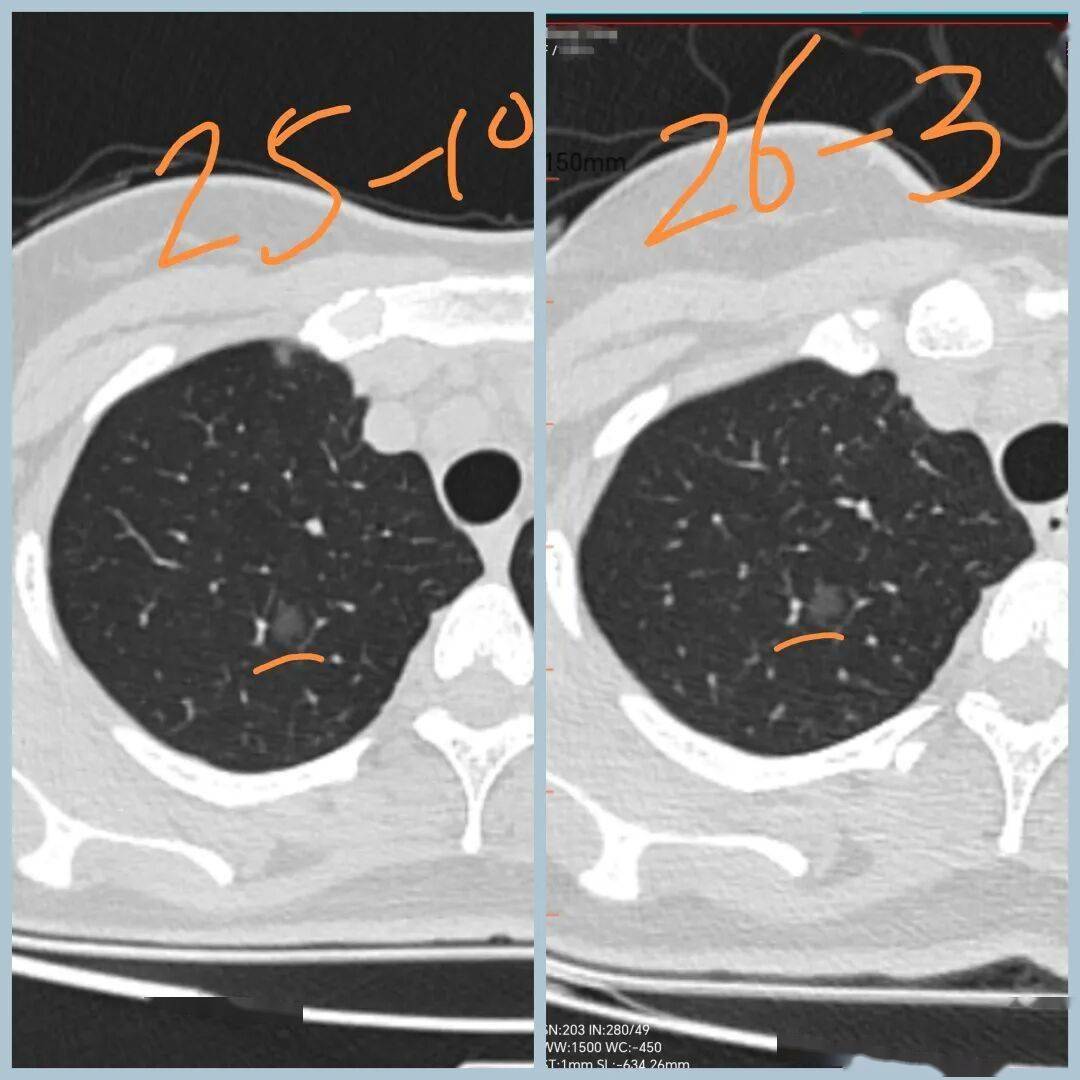

【病例3,网络咨询】

女性,30+,发现双肺结节5个月

分别是右肺上叶纯磨玻璃结节,大小约8mm

左肺下叶实性结节,大小约1cm

5个月后复查,右肺磨玻璃结节无变化,左肺实性结节增大

下一步怎么办:

1、磨玻璃结节无增大,原位癌可能,可继续观察

2、左下叶结节增大,有可能是低度恶性肿瘤,如类癌。也可能是良性病变,如错构瘤、硬化性肺泡细胞瘤。半年后再复查,继续增大,建议手术。

3、手术方式可 尝试剥除,若无法剥除,或为恶性,则行肺叶切除。